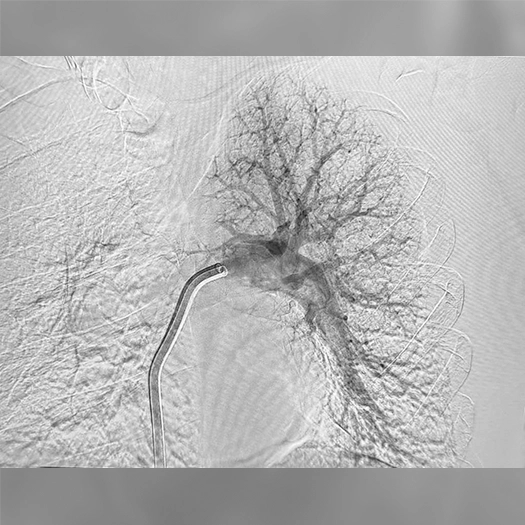

Pulmonary Embolism Cases